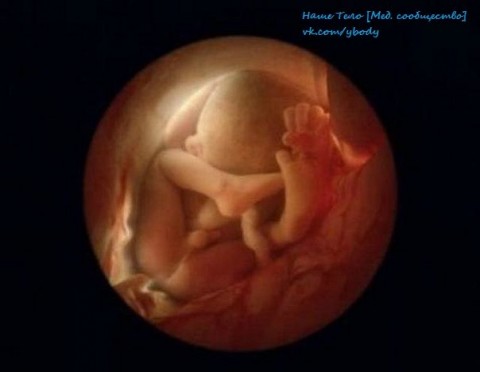

Шведский фотограф Леннарт Нилссон сделал свои первые

фотографии еще в 1965 году. Он потратил 10 лет жизни, чтобы снять на

пленку эволюцию эмбриона от зачатия до рождения. Уникальные кадры с

места, откуда люди делают первый шаг в мир.

8 недель. Быстрорастущий эмбрион хорошо защищен во чреве

матери. С помощью электронного микроскопа Нильссон смог увеличить

изображение в сотни тысяч раз

6 месяцев. Впереди еще восемь-десять беззаботных недель

36 недель. Через 4 недели ребенок увидит белый свет Источник